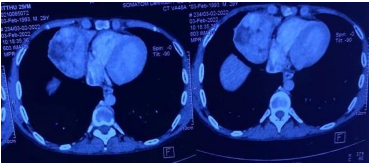

A 29-year-old male presented in outpatient department with complaints of intermittent cough with dull aching chest pain. Patient was evaluated at some Pulmonary clinic where CT (Computerized Tomography) guided lung biopsy was taken, which revealed moderate pleomorphism, mitosis present, focal hemorrhage. To differentiate better immunohistochemistry was done, which was positive for Pan CK, LCA and Ki67. It was negative for CK7, CK20, Chromogranin. CECT (Contrast Enhanced Computerized Tomography Chest) suggestive of Anterior mediastinal mass (Figure 1) 6.7x6.0x9.0 cm with SUV max 2.6 and abutting the SVC & RA. PET-CT (Positron Emission Tomography) suggestive of no distant metastasis (Figure 2). Tumor markers CA 19-9, AFP, B-HCG 1.4, CA 125 was within normal limit. Diagnosis of Type A Thymoma was established. He was planned for elective surgery. A Midline Sternotomy was performed and tumor was resected en-mass. It measured approximately 12x8 cm with areas of hemorrhage. It did not invade pleura, pericardium, heart and great vessels. Postoperative recovery was uneventful (Figure 3). He was asymptomatic at 3 months of follow up.

Figure1: Preoperative CT Scan images showing anterior mediastinal mass, thymoma